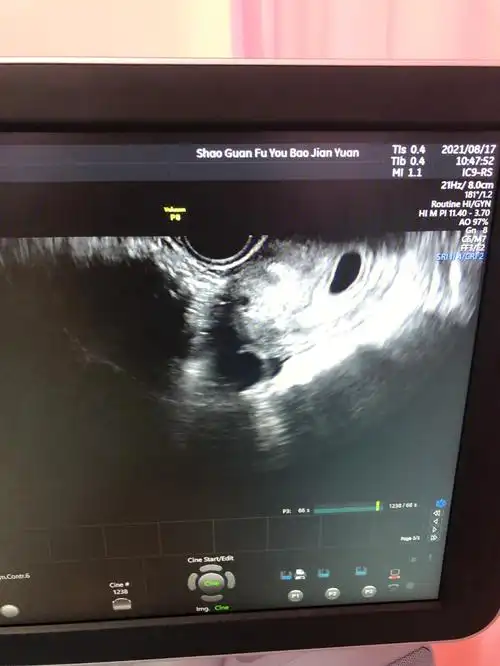

试管之路 移植18天,b超显示有两个孕囊,喜忧参半,一大一小.

孕47天一超,可见孕囊18×15mm,胚芽8.

移植3天冻胚胎2枚,看到一枚孕囊,圈起来是右边,不知道是宫外孕还是

第一次b超